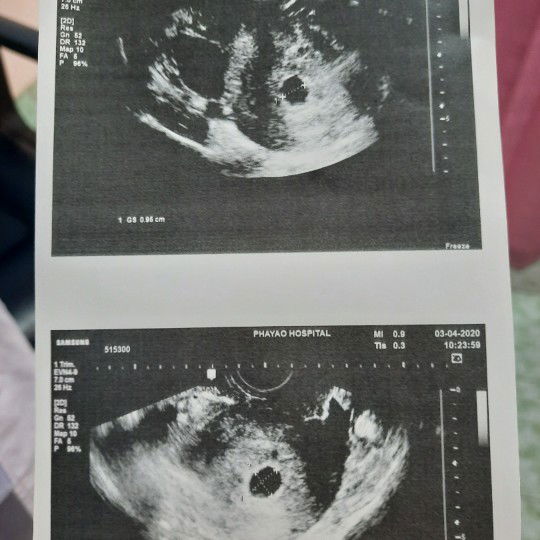

พอมีหวังจะเจอน้องอยู่มั้ยคะ

เมื่อวันที่18.03.63ซื้อที่ตรวจครรภ์มาตรวจตอนเช้าขึ้นสองขีดจาง ๆ วันที่ 20.03.63 ไปตรวจที่ รพ. หมอบอกว่าท้อง แต่อัลตร้าซาวด์ทางช่องคลอดก็ไม่เจออะไร วันนี้ 03.04.63 หมอที่ รพ.นัดไปตรวจ วันนี้อัลตร้าซาสด์เห็นแค่ถุงแบบนี้พอมีหวังจะเจอน้องอยู่มั้ยคะ